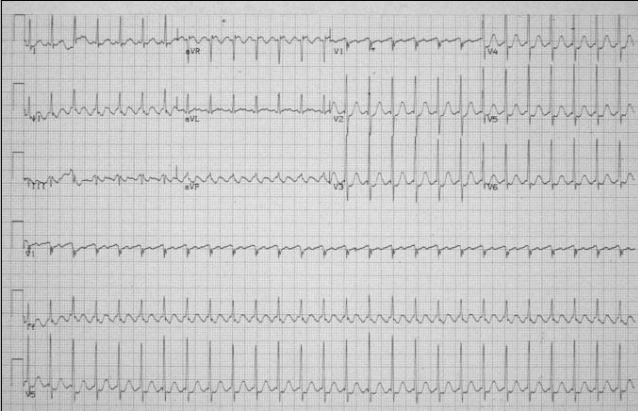

What is this?

Atrial flutter